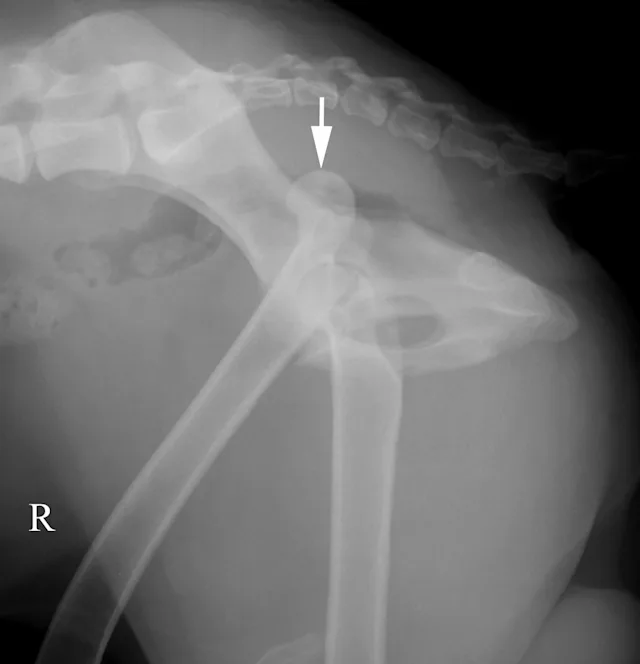

The lateral radiograph is obtained with the patient in lateral recumbency and the hindlimbs separated (Figure 3A). A foam positioning device is placed between the limbs or under the "up" leg to keep the femur parallel to the table. The forward limb (typically the limb closest to the imaging plate) is labeled. The corresponding normal lateral radiograph is shown in Figure 3B. In Figure 3C, the femoral head (arrow) of the cranially positioned right limb is luxated craniodorsally.